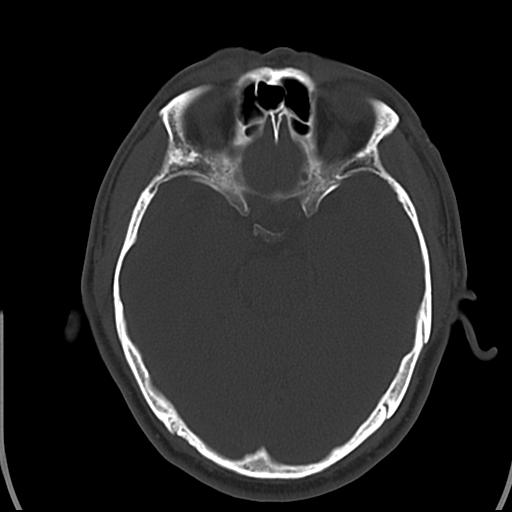

头皮下高密度结节影???临床上在老年男性比较常见。大家看看是什么?成因是? 本例患者,男性,51岁。外伤来诊。无染发史及发根植入史。

考虑异物。

皮下钙化点

没见过,可能为毛囊钙化。

考虑钙化。